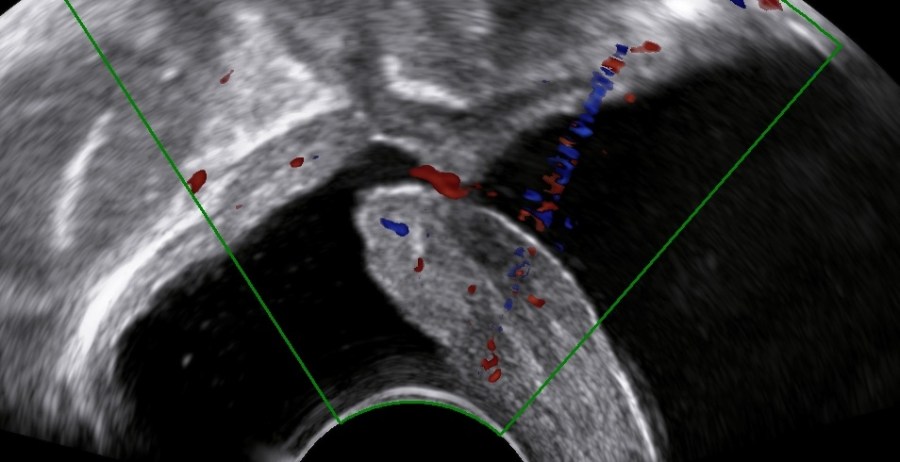

The levator ani muscle avulsion may be demonstrated with 2D Ultrasound, however 3D (or even 4D) Ultrasound as well as MRI are superior in demonstrating avulsion (Dietz 2019).